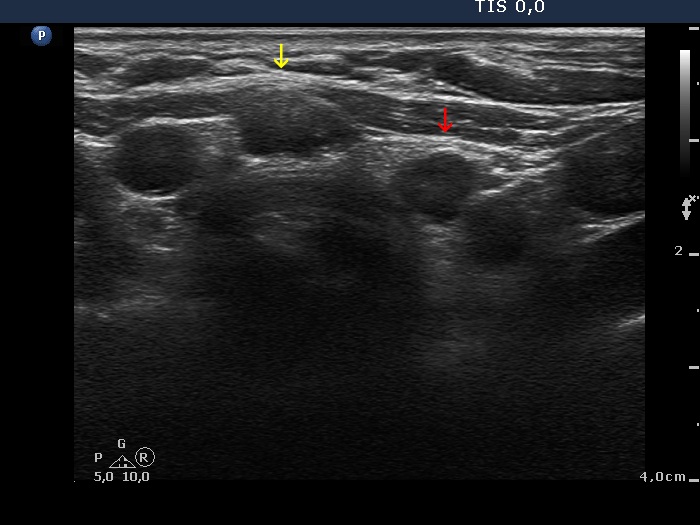

Right lobe, longitudinal scan

Isthmus and left lobe, transverse view. The lesion in the isthmus is signed with yellow while that in the left lobe is with red arrow.